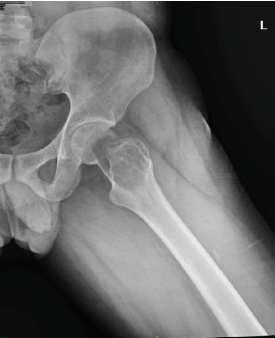

Combined Approach (Surgery + Systemic Adjuvant Therapy) in a Giant Cell Tumor of Proximal Femur: A Rare Case Report

Prithvi Mohandas , Sunil D Magadum , M Manickavasagam

………………………………p.179-185